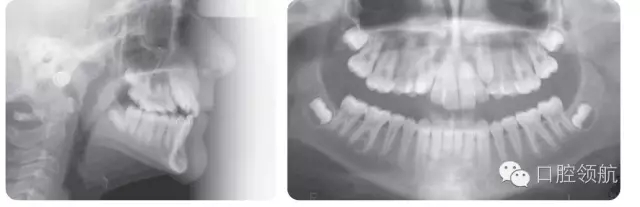

14歲男性患者,安氏I類咬合關(guān)系,輕度骨性II類長(zhǎng)面型,嚴(yán)重的上牙列擁擠,上尖牙唇側(cè)錯(cuò)位,雙側(cè)后牙反,前牙淺覆牙合(圖3.13)。

● 上頜快速擴(kuò)弓(圖3.14)。